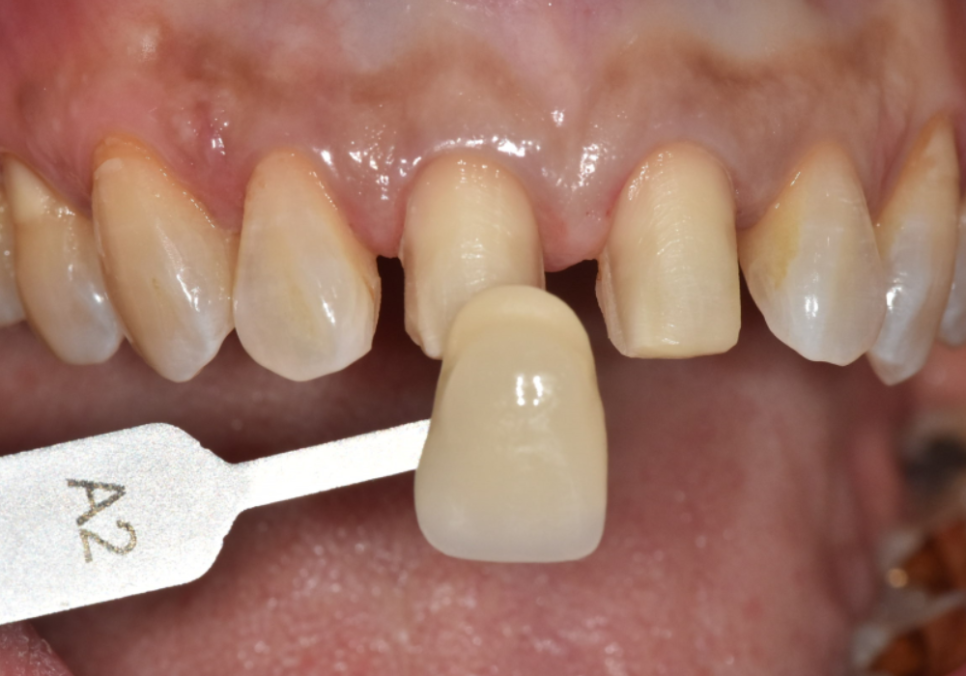

레진 재치료보다 라미네이트를 선택한 이유

고덕동 치과 누런 이, 앞니 사이 틈, 잘못된 관리 때문일까?

앞니 사이 틈과 치아 변색을

함께 개선하기 위해

레진 재치료도 고려할 수 있었지만,

잇몸이 더 내려가면

다시 틈이 생길 가능성이 높고

레진은 시간이 지나며

변색과 마모가 비교적 빠른 편이기 때문에

이번 경우에는

라미네이트 치료가 더 적절하다고 판단했습니다.

라미네이트는

얇은 세라믹 보철을 치아 겉면에 부착해

치아의 색상과 형태를 함께 개선할 수 있어,

블랙 트라이앵글과 치아 변색을

동시에 보완할 수 있는 치료 방법입니다.

라미네이트 제작 과정

원내 기공소가 있는 치과의 차이

저희 치과는

원내 기공소를 직접 운영하고 있습니다.

외부 기공소를 이용하는 경우에는

보철 제작과 수정 과정에서

기공물이 오가며 배송 기간을 기다려야 해

치료 기간이 길어지는 경우가 많습니다.

반면 원내 기공소에서는

의료진, 기공사, 환자분이 직접 소통하며

색상이나 모양이 조금이라도 마음에 들지 않으면

그 자리에서 바로 수정이 가능합니다.

250318

이 환자분 역시

치아 색감과 투명도에 대해

세밀한 의견을 주셨고,

250318 (전) 250325 (후)

즉각적인 피드백을 반영해

자연스럽고 조화로운 앞니 라인이

완성되었습니다. ^^